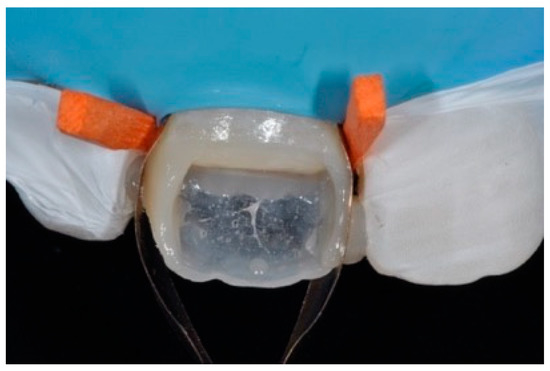

Step 3 (adhesive procedure): After frame modification, dust was removed with strong air pressure and internal surface was treated with a silane coupling agent (Monobond Plus, Ivoclar Vivadent, Schaan, Liechtenstein) applied with a microbrush in a thin layer and allowed to react for 60 s. An adhesive (OptiBond FL, Kerr, Bioggio, Switzerland) was applied following manufacturer’s instructions, and photoactivated for 20 s (Figure 9).

Figure 9.

After frame modification silane coupling agent and adhesive procedures are applied. Reprinted from Restauri diretti nei settori anteriori, G. Paolone, S. Scolavino, © 2021, with permission from Quintessence Publishing Italy.